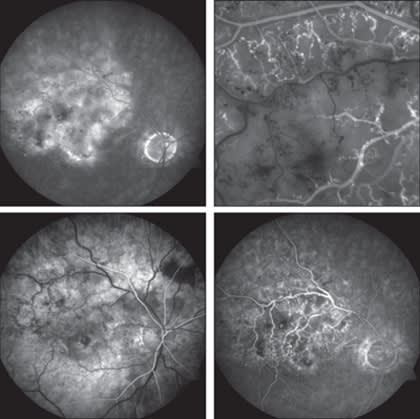

Figure 1. Typical nonischemic central retinal vein occlusion in the left eye of a 48-year-old African-American male.